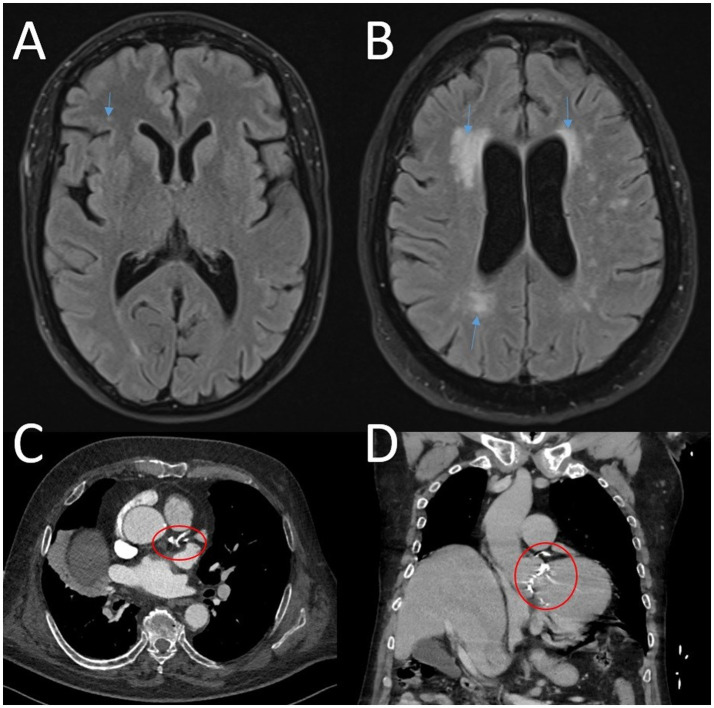

Background: A connection between cerebral white matter hyperintensities and coronary artery disease is widely discussed. Both conditions are more prevalent in the elderly. While white matter hyperintensities are often associated with small vessel disease, atherosclerosis is the primary cause of coronary artery disease.

Methods: We evaluated staging CT scans of the body and staging brain MRIs from patients with newly diagnosed malignant melanoma (without metastasis) between 01/01/2015 and 06/30/2023. CT scans were assessed for coronary artery disease using a modified overall visual assessment. Fazekas scores were used to evaluate the MRI for white matter changes. Additional clinical data were obtained from digital patient records.

Results: We analyzed data from 120 patients (57 females, mean age 68 years, standard deviation 14 years) and found a correlation between coronary artery disease and both age (r = 0.48, α = 0.04) and Fazekas score (periventricular r = 0.46, subcortical and deep white matter r = 0.55). A linear model including age, coronary artery disease, diabetes and arterial hypertension served as a predictor for white matter disease and showed significant correlations. Adding (1) atherosclerosis as well as (2) carotid stenosis to the model resulted in (1) a slight decrease in significance and (2) the unmasking of a potential spurious correlation with carotid stenosis.

Conclusion: There is a significant correlation between white matter hyperintensities and both carotid stenoses and coronary artery disease. This finding is clinically relevant: in patients with white matter hyperintensities and coronary artery disease, carotid stenosis should be ruled out.